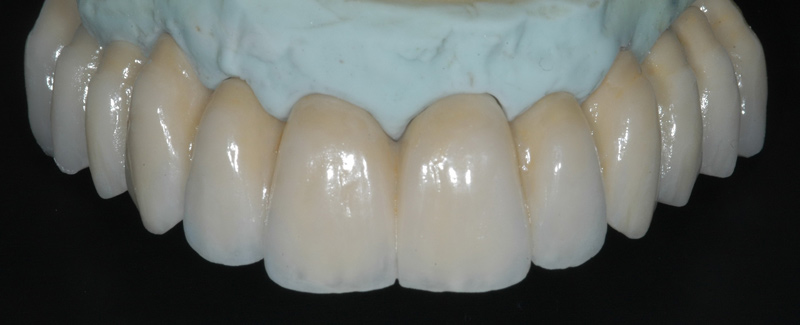

Protesi fissa estetica su impianti e denti naturali (*)

Il successo nel tempo degli impianti dentali dipende oltre che dal lavoro del dentista implantologo anche dalla qualità e dalla tipologia del lavoro protesico; pertanto consapevoli di ciò e servendoci dell’eccellenza dei laboratori odontotecnici italiani eseguiamo e garantiamo le seguenti tipologie di protesi fisse su impianti e denti naturali:

- protesi fissa in zirconia monolitica

- protesi fissa in zirconia ceramica

- protesi fissa in metallo ceramica

- protesi fissa in metallo composito